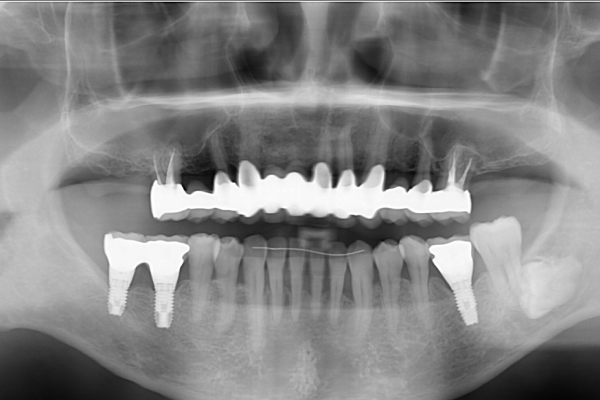

- 性別年齢

- 男性:68歳

- 治療内容

- インプラントを上下顎の奥歯に7本

- 金額

- 330万円(税込)

- 来院理由

- 歯周病が進行してきたため、噛めなくなってきた。インプラントを含めて総合的にきちんとした専門医の治療を受けたい。

- 施術の

副作用

(リスク) - 経過とともになくなりますが、術直後に腫れや違和感を感じることがあります。